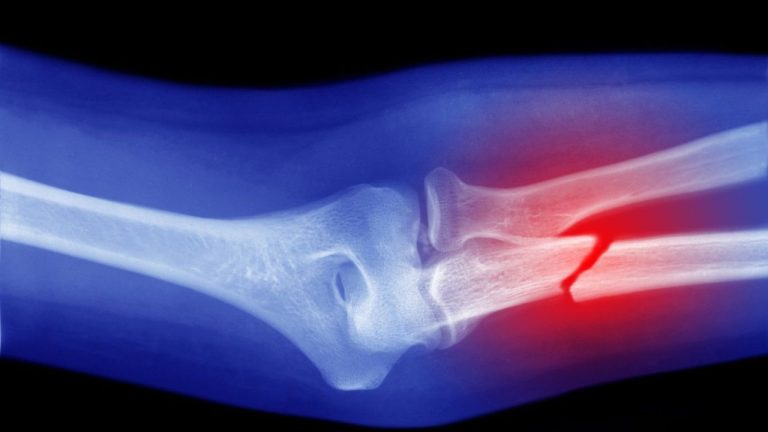

• Beda Fisioterapi dan Kemoterapi, sudah pasti ada pada bagian faktor utamanya, yaitu, Fisioterapi berfokus pada tulang, jaringan lunak, dan sendi. Contohnya gangguan yang umumnya terjadi di masyarakat, antara lain, sakit leher, sakit bahu, sakit punggung dan cedera olahraga.

Bagaimana Cara Merawat Tulang Cedera atau Rawan?

Setelah memahami benar beda Fisioterapi dan Kemoterapi, dapat disimpulkan juga jika penyakit kanker timbul akibat faktor diri sendiri atau lingkungan. Lalu, bagaimana dengan cara merawat tulang cedera atau rawan?

Bagi Anda yang memiliki permasalahan seputar tulang, jangan khawatir dan berputus asa. Sebab, Fisioterapi dari layanan Mitra Fisiohome siap memberikan kesembuhan berdasarkan prosedur dibawah ahli profesional.